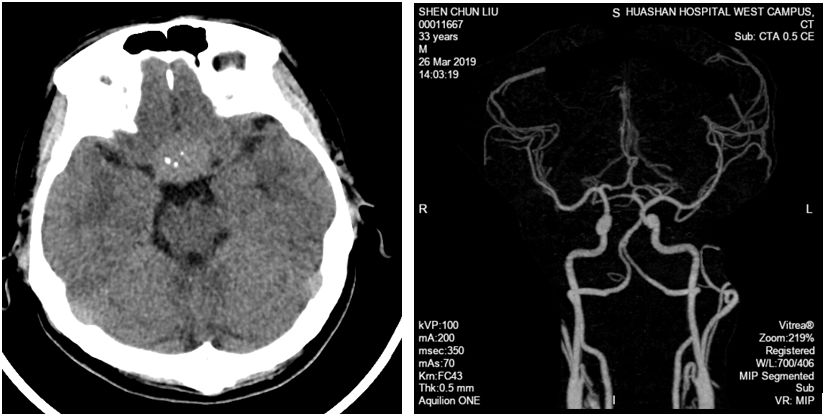

患者,男性,32岁;

主诉:视物模糊1个月;

体检: VOU 0.12,双眼颞侧偏盲,左眼甚。

- 术前诊断

鞍结节脑膜瘤

- 手术方案

左侧改良翼点开颅,内镜辅助肿瘤切除